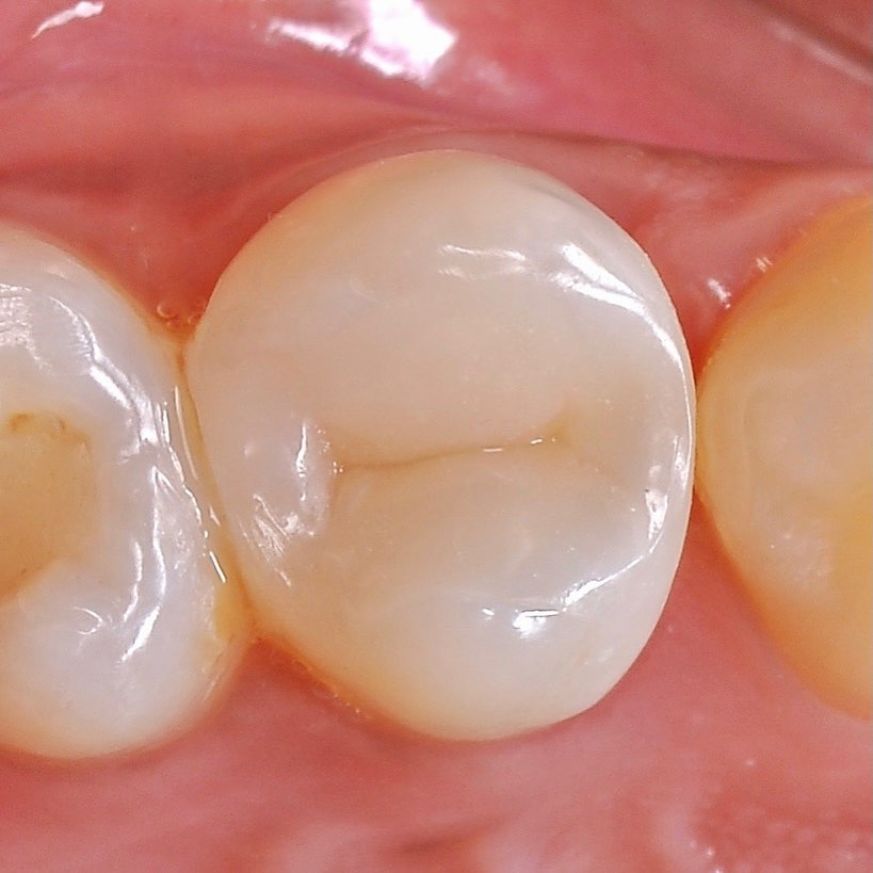

устанавливаем коронку на вылеченный зуб

Протезируем зуб, защищаем его от внешней среды

зуб с обработанными каналами